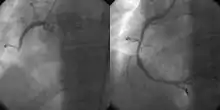

![]() A coronary angiogram showing the circulation in the left main coronary artery and its branches. | |